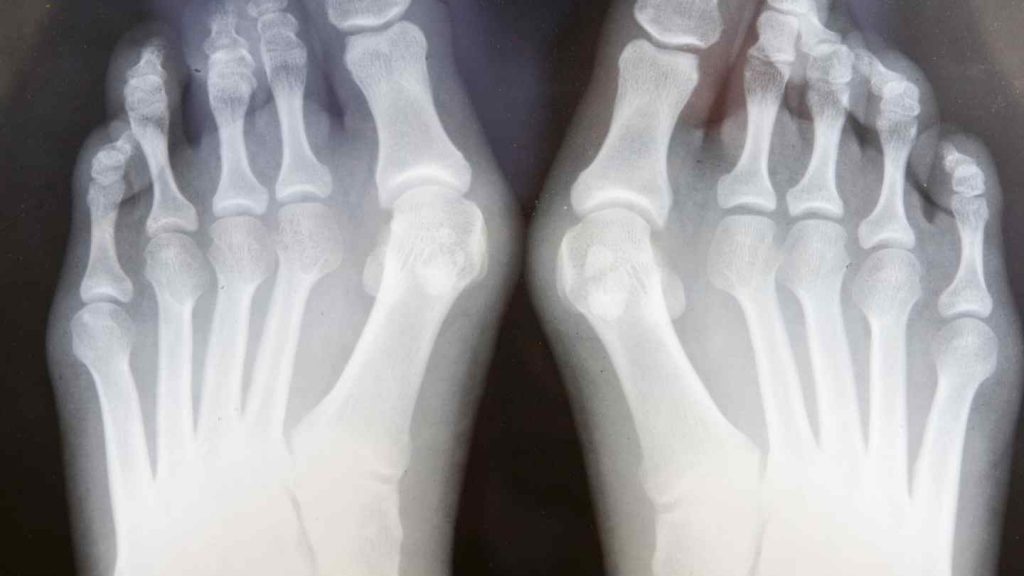

Το κότσι είναι ένα ψευδο-οστέινο εξόγκωμα που σχηματίζεται στη βάση του μεγάλου δακτύλου του ποδιού σας. Αυτός ο τύπος κάλου αναπτύσσεται στο εσωτερικό άκρο της άρθρωσης του μεγάλου δακτύλου του ποδιού σας – της μεταταρσοφαλαγγικής άρθρωσης (MTΦ).

Η άρθρωση MTΦ είναι το σημείο όπου η βάση του μεγάλου δακτύλου του ποδιού σας συναντά τον υπόλοιπο άκρο πόδα Ο ιατρικός όρος για το κότσι είναι hallux valgus.

Ο επαγγελματίας υγείας ίσως χρησιμοποιήσει ακτινογραφίες ποδιών για να προσδιορίσει τη συνολική ευθυγράμμιση των οστών σας και της άρθρωσης MTΦ, καθώς και το πραγματικό μέγεθος που έχει το κότσι.